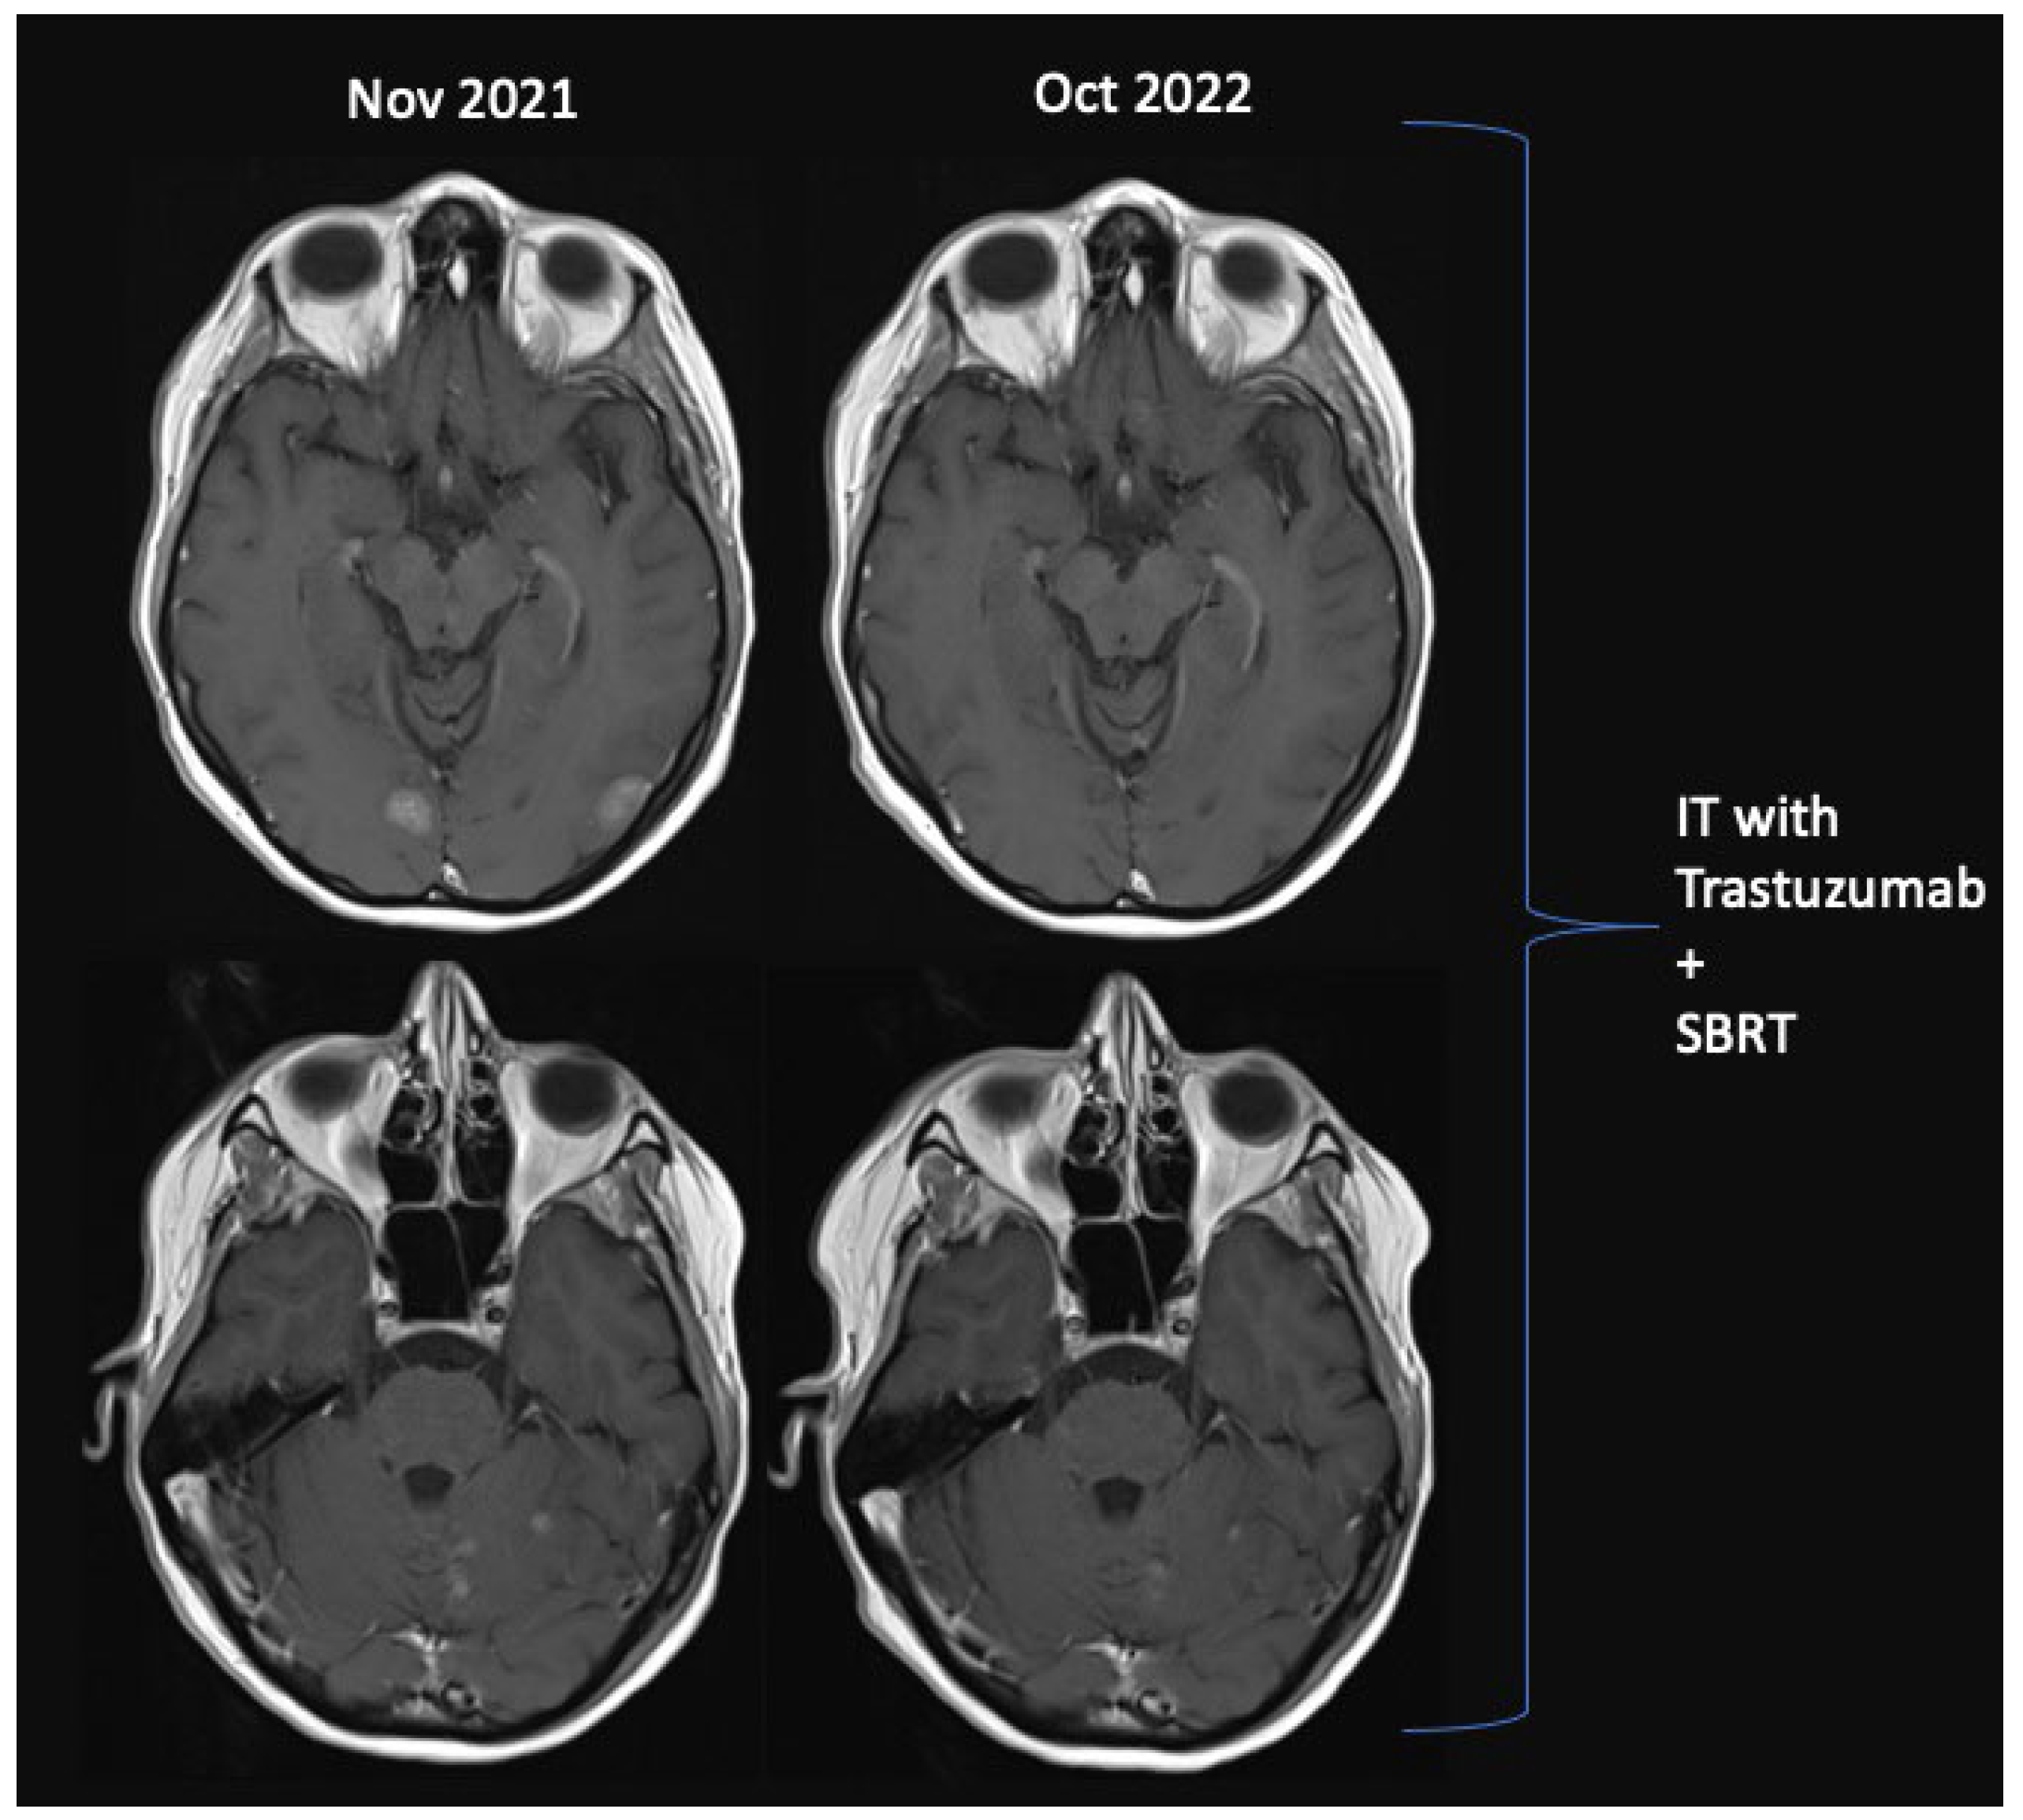

| 1. | 54 | 100 | 13 | Yes | Yes | Yes | 41 | C | 12 | No | Tucatinib-Capecitabine-Trastuzumab | 18 | 19 |

| 2. | 38 | 100 | No BM | No | No | Yes | 0 | B | 35 | No | Tucatinib-Capecitabine-Trastuzumab | 24 | 24 |